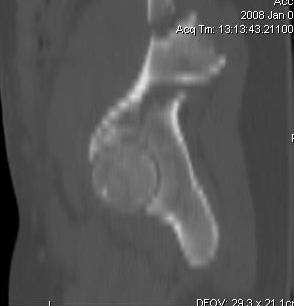

Уважаемые коллеги! С прошедшеми Вас праздниками. Теперь ближе к трудовым будням. Поступила 16 летняя девушка неделю назад. Механизм травмы падение с 5 этажа. Краткий диагноз:закрытый перелом левой ключицы, левого плеча, закрытый вертикально и ротационно нестабильный перелом костей таза:закрытый перелом левой подвздошной кости, переломы лонной кости справа, перелом обоих колонн вертлужной впадины слева;субкапитальный перелом шейки левой бедренной кости со смещением. По тактике лечения таза возникли следующие вопросы: 1. С чего начать - фиксации переломов вертлужной впадины или устранения деформаций таза? 2. Надо ли фиксировать шейку или фиксировать бедро в аппарате вместе с тазом, а после сращения таза планировать ТЭП ТБС? Если имеются еще какие подводные камни, будем рады выслушать.Спасибо.

На снимке ацетабулума редко встречающийся очень низкий перелом, наверное, трудно было репозицию через один доступ? Перелом как бы замкнулся в квадрилатеральной поврехности.

Ничего такого особенного в переломе вертлужной впадины не опознал. Транстектальный перелом хорошо репонируется щипцами, установленными через седалищную вырезку.